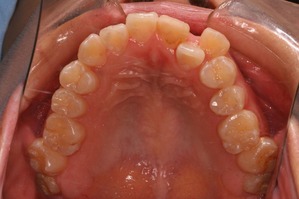

上方向からみると奥歯が頬方向に傾いております。

つまり例としては1と3に当てはまります。

上の奥歯の部分を注目してください。親知らずの前の歯が2本抜歯してるのがわかると思います。

つまり、この時点で上顎だけで3本も抜歯してます。そういう意味では患者さんは不安になりますかね(笑)